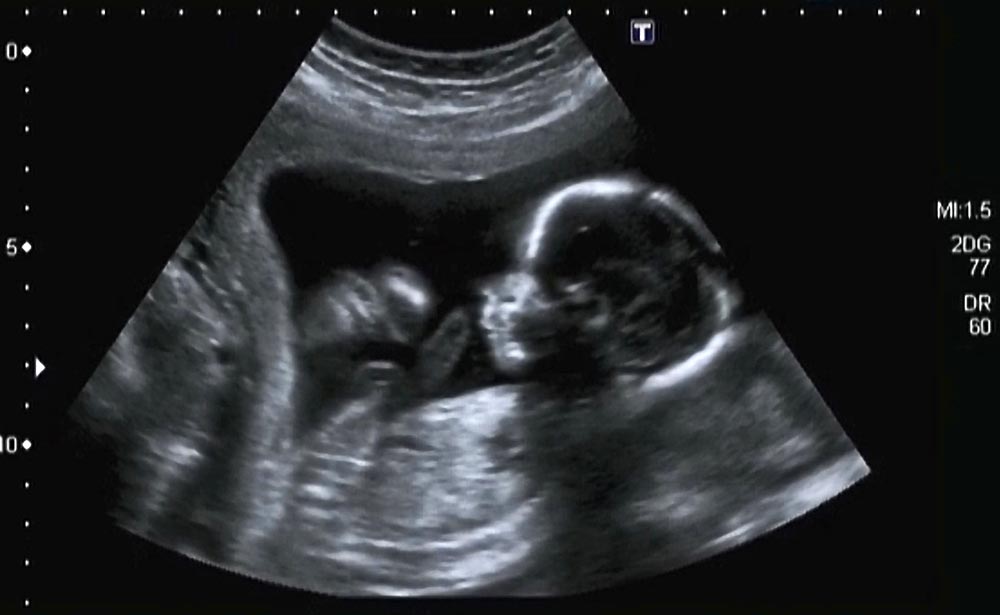

Pour que la mesure soit validée, l’embryon doit avoir une taille spécifique. Le médecin mesure d’abord la Longueur Crânio-Caudale (LCC), soit la distance tête-fesses.

La LCC de l’embryon doit être strictement comprise entre 45 et 84 mm. De plus, la mesure doit être faite exclusivement sur une coupe sagittale stricte de l’embryon (de profil parfait), avec la tête en position neutre. Si le fœtus est recroquevillé ou a la tête trop en extension, la mesure de la nuque sera faussée. L’échographiste devra alors patienter et faire bouger la mère.

Comment la clarté nucale est-elle mesurée par le médecin ?

L’échographiste doit obtenir une coupe sagittale stricte (un profil parfait du bébé, tête non fléchie). Il place ses curseurs à l’endroit le plus large de l’espace liquidien situé entre la peau et les tissus sous-cutanés de la nuque.